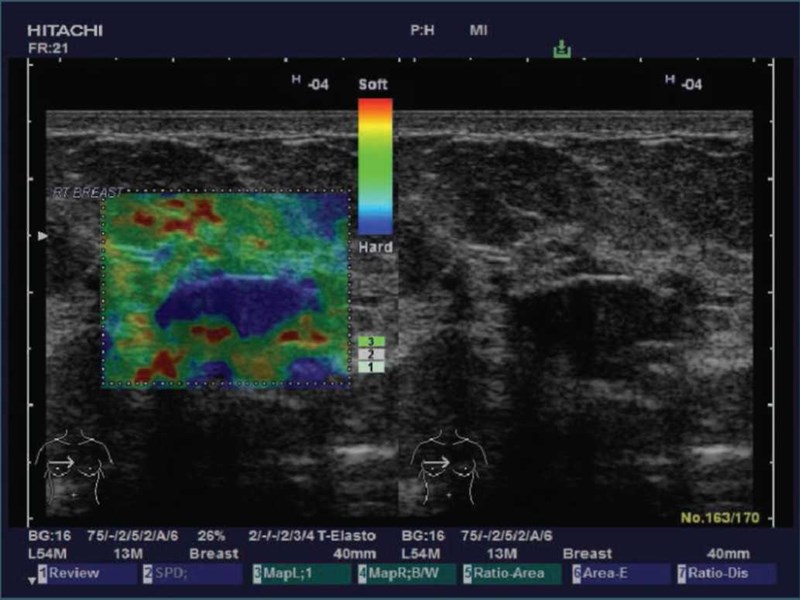

Η ελαστογραφία ειναι μία απεικονιστική μέθοδος υπερήχων (αλλά και μαγνητικού τομογράφου) που χαρτογραφεί την ελαστικότητα ενός ιστού. Ειδικότερα, χρησιμοποιείται για την εκτίμηση της σκληρότητας (stiffness) συγκεκριμένων εστιακών αλλοιώσεων (θυρεοειδής, μαστός ) αλλά και για την εκτίμηση της ελαστικότητας ολοκλήρων οργάνων (ήπαρ). Για παράδειγμα, οι κακοήθεις αλλοιώσεις παρουσιάζονται με μειωμένη ελαστικότητα σε σχέση με τον γειτονικό υγιή ιστό, ενώ η διάχυτη ηπατική νόσος παρουσιάζει αυξημένη σκληρότητα απο ένα υγιές ήπαρ.

Οπως ειπώθηκε, η ελαστογραφία χρησιμοποιείται κυρίως για την διερεύνηση όζων στον θυρεοειδή αδένα, οζωδών αλλοιώσεων στον μαστό ενώ έχει εφαρμογή και σε εστιακές αλλοιώσεις τόσο στον προστάτη όσο και στους όρχεις. Επίσης χρησιμοποιείται στο ήπαρ για την διερεύνηση διάχυτης ηπατικής νόσου. Eκτός της διαγνωστικής προσέγγισης η ελαστογραφία χρησιμοποιείται και σαν οδηγός στην ανεύρεση συγκεκριμένου σημείου βιοψίας αλλά και για να περιορίσει τον υπερβολικό αριθμό αυτών καθώς σε πολλές περιπτώσεις δίνει σαφή εικόνα της δομής μίας αλλοίωσης. Με την πάροδο του χρόνου και την εξέλιξη της τεχνολογίας, ολο και λιγότερες βιοψίες καθίστανται αναγκαίες καθώς αντικαθίστανται από μία ανώδυνη, αναίμακτη και ακίνδυνη μέθοδο με υψηλά ποσοστά αξιοπιστίας. Ειδικότερα στο ήπαρ που μία βιοψία είναι εξέταση υψηλού ρίσκου, η ελαστογραφία μπορεί να δώσει ακίνδυνη και πολύ αξιόπιστη λύση. ΠΩΣ ΛΕΙΤΟΥΡΓΕΙ Υπάρχουν αρκετές τεχνικές ελαστογραφίας ενώ ειναι σε ανάπτυξη και αρκετές νεώτερες. Ολες όμως οι τεχνικές εχουν κοινό σημείο την ανάπτυξη μίας μηχανικής διέγερσης του προς εξέτασιν ιστού και παρακολούθηση και καταγραφή της αντίδρασης του είτε ως εικόνα είτε ως μέτρηση δεδομένων. Oι δύο κυριότερες και πιο διαδεδομένες τεχνικές είναι η strain elastography και η share wave elastography. Στην πρώτη, με την βοήθεια του ηχωβολέα, δημιουργούμε μια εξωτερική πίεση στους ιστούς, η οποία μεταδίδεται στην προς εξέτασιν περιοχή και καταγράφεται απεικονιστικά και χρωματικά η αντιδραση της. Στην δεύτερη, ένα ηχητικό κύμα παράγεται εντός του ιστού που διερευνούμε και εξετάζουμε την ταχύτητα μετάδοσης του σε σχέση με το γειτονικό υγιές παρέγχυμα, κρίνοντας έτσι την ελαστικότητα του σε σχέση με αυτό.